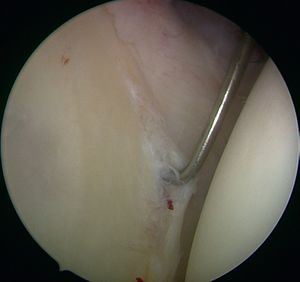

This progressive avulsion is taken-up by Burkhart et al. as the aptly termed ‘peel-back mechanism’ observed by reproducing the cocking phase under arthroscopic control, confirming the medial pivot of the posterosuperior labrum around the posterosuperior glenoid rim (Figure and Video).[6]

Peel-back mechanism

The beach-chair or supine position, with the arm free and not in traction, allows for dynamic tests under arthroscopic control; traction is then optional. The posterior approach (soft point) is lower than usual and slightly lateral, allowing a good view of the posterior labrum. The anterior approach in the rotator interval allows the insertion of a probe to confirm the need for repair. There are three signs required for positive arthroscopic diagnosis of a superior labral tear from anterior to posterior (SLAP) II lesion: a positive peel-back sign during dynamic cocking (the arm is abducted at 90 degrees and externally rotated at 90 degrees), a sublabral sulcus palpation > 5mm deep and a mobile labrobicipital complex. Two secondary instrumental incisions may be performed as required, using a small sleeve (spear guide < 4 mm), which is less traumatic for the rotator cuff and allows threading of anchors. The antero-lateral approach facilitates antero-superior anchoring of the glenoid rim (with an approach angle of 45 degrees) and the posterolateral Wilmington approach (1 cm from the posterolateral acromion angle and 1cm forward) allowing an angle of approach of 45 degrees to the posterosuperior angle of the glenoid).[55]